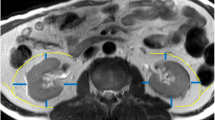

A retrospective analysis was conducted on fat-selective magnetic resonance images (MRI) from 319 individuals with a BMI ≥24 kg/m². Participants were categorized into four groups: solely obesity, T2DM, hypertension, and dyslipidemia, to examine differences in the distribution of hepatic, pancreatic, preperitoneal, mesenteric, and perirenal fat (PrFT). Correlation analyses were performed to elucidate relationships between visceral fat deposits and obesity-related characteristics. Logistic regression identified key fat deposition sites associated with common obesity-related complications. Additionally, the limitations of single-site fat measurements in capturing the heterogeneity of obesity were examined.

PrFT exhibited the strongest correlation with blood pressure (r = 0.225 ~ 0.306, all p < 0.001) among all visceral fats, and the hypertensive individuals with obesity presented the highest PrFT. Hepatic fat showed the highest association with glucose metabolism (r = 0.188 ~ 0.407 all p < 0.01), as evidenced by higher hepatic fat content in the T2DM group compared to other groups. Risk of metabolic syndrome increased by 3.06-fold (95% CI:1.35–6.93, p = 0.007) and 6.79-fold (95% CI:2.45–18.83, p < 0.001) with moderate and severe fatty steatosis compared to those without hepatic steatosis. A 2.24-fold (95% CI:1.27–3.97, p = 0.006) increase in metabolic syndrome likelihood was observed for each 1 cm increment in PrFT.

Besides hepatic fat, perirenal fat is also a key determinant for metabolic syndrome. Patients with various metabolic abnormalities present distinct patterns of visceral fat distribution, which could be simply profiled by perirenal and hepatic fat quantification.